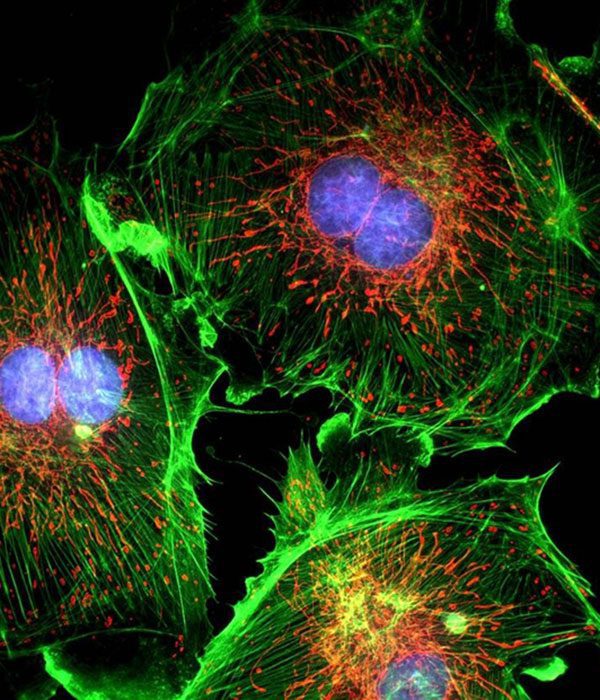

- General and specialized tissue and cell staining

- Immunocytochemistry (ICC) technique